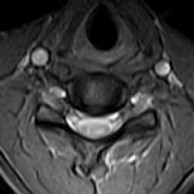

• There is a loss of the normal ventral bulge (flattened) of the cervical spinal cord, more so to the right over the C5 to C7 levels. Hyperintense signal, best appreciated on the GRASS axial images is seen within the cervical spinal cord, ventrally (anterior horn cells) over these levels.